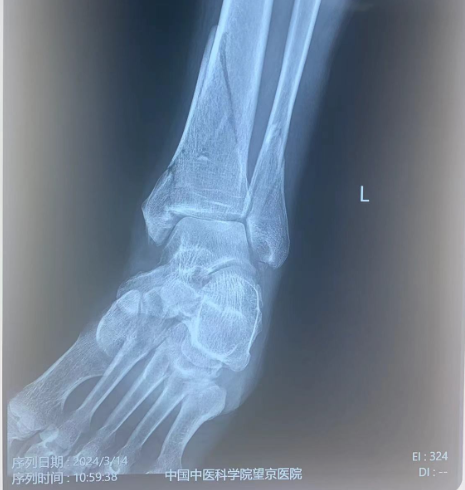

本病例左三踝骨折。術(shù)前正側(cè)位片:脛骨遠(yuǎn)端骨折。

術(shù)前X光片: